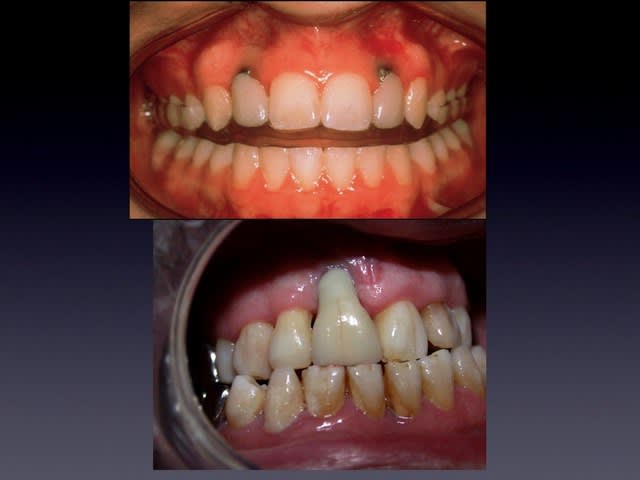

Ce serait sympa de nous mettre des photos , bouche ouverte et un sourire naturel car si elle ne découvre pas beaucoup, que l'ortho est bien faite en laissant le Parodonte en place. Pour ce, couper les fibres circulaires et Traction Forte; genre on ouvre une bouteille de Rioja. Je me demande si la Chir Paro est necessaire

Pour le sourire, levres tres hypotoniques, a la monica, elle ne decouvre pas du tout les collets.

Mais elle fera chier s'il y a une difference.